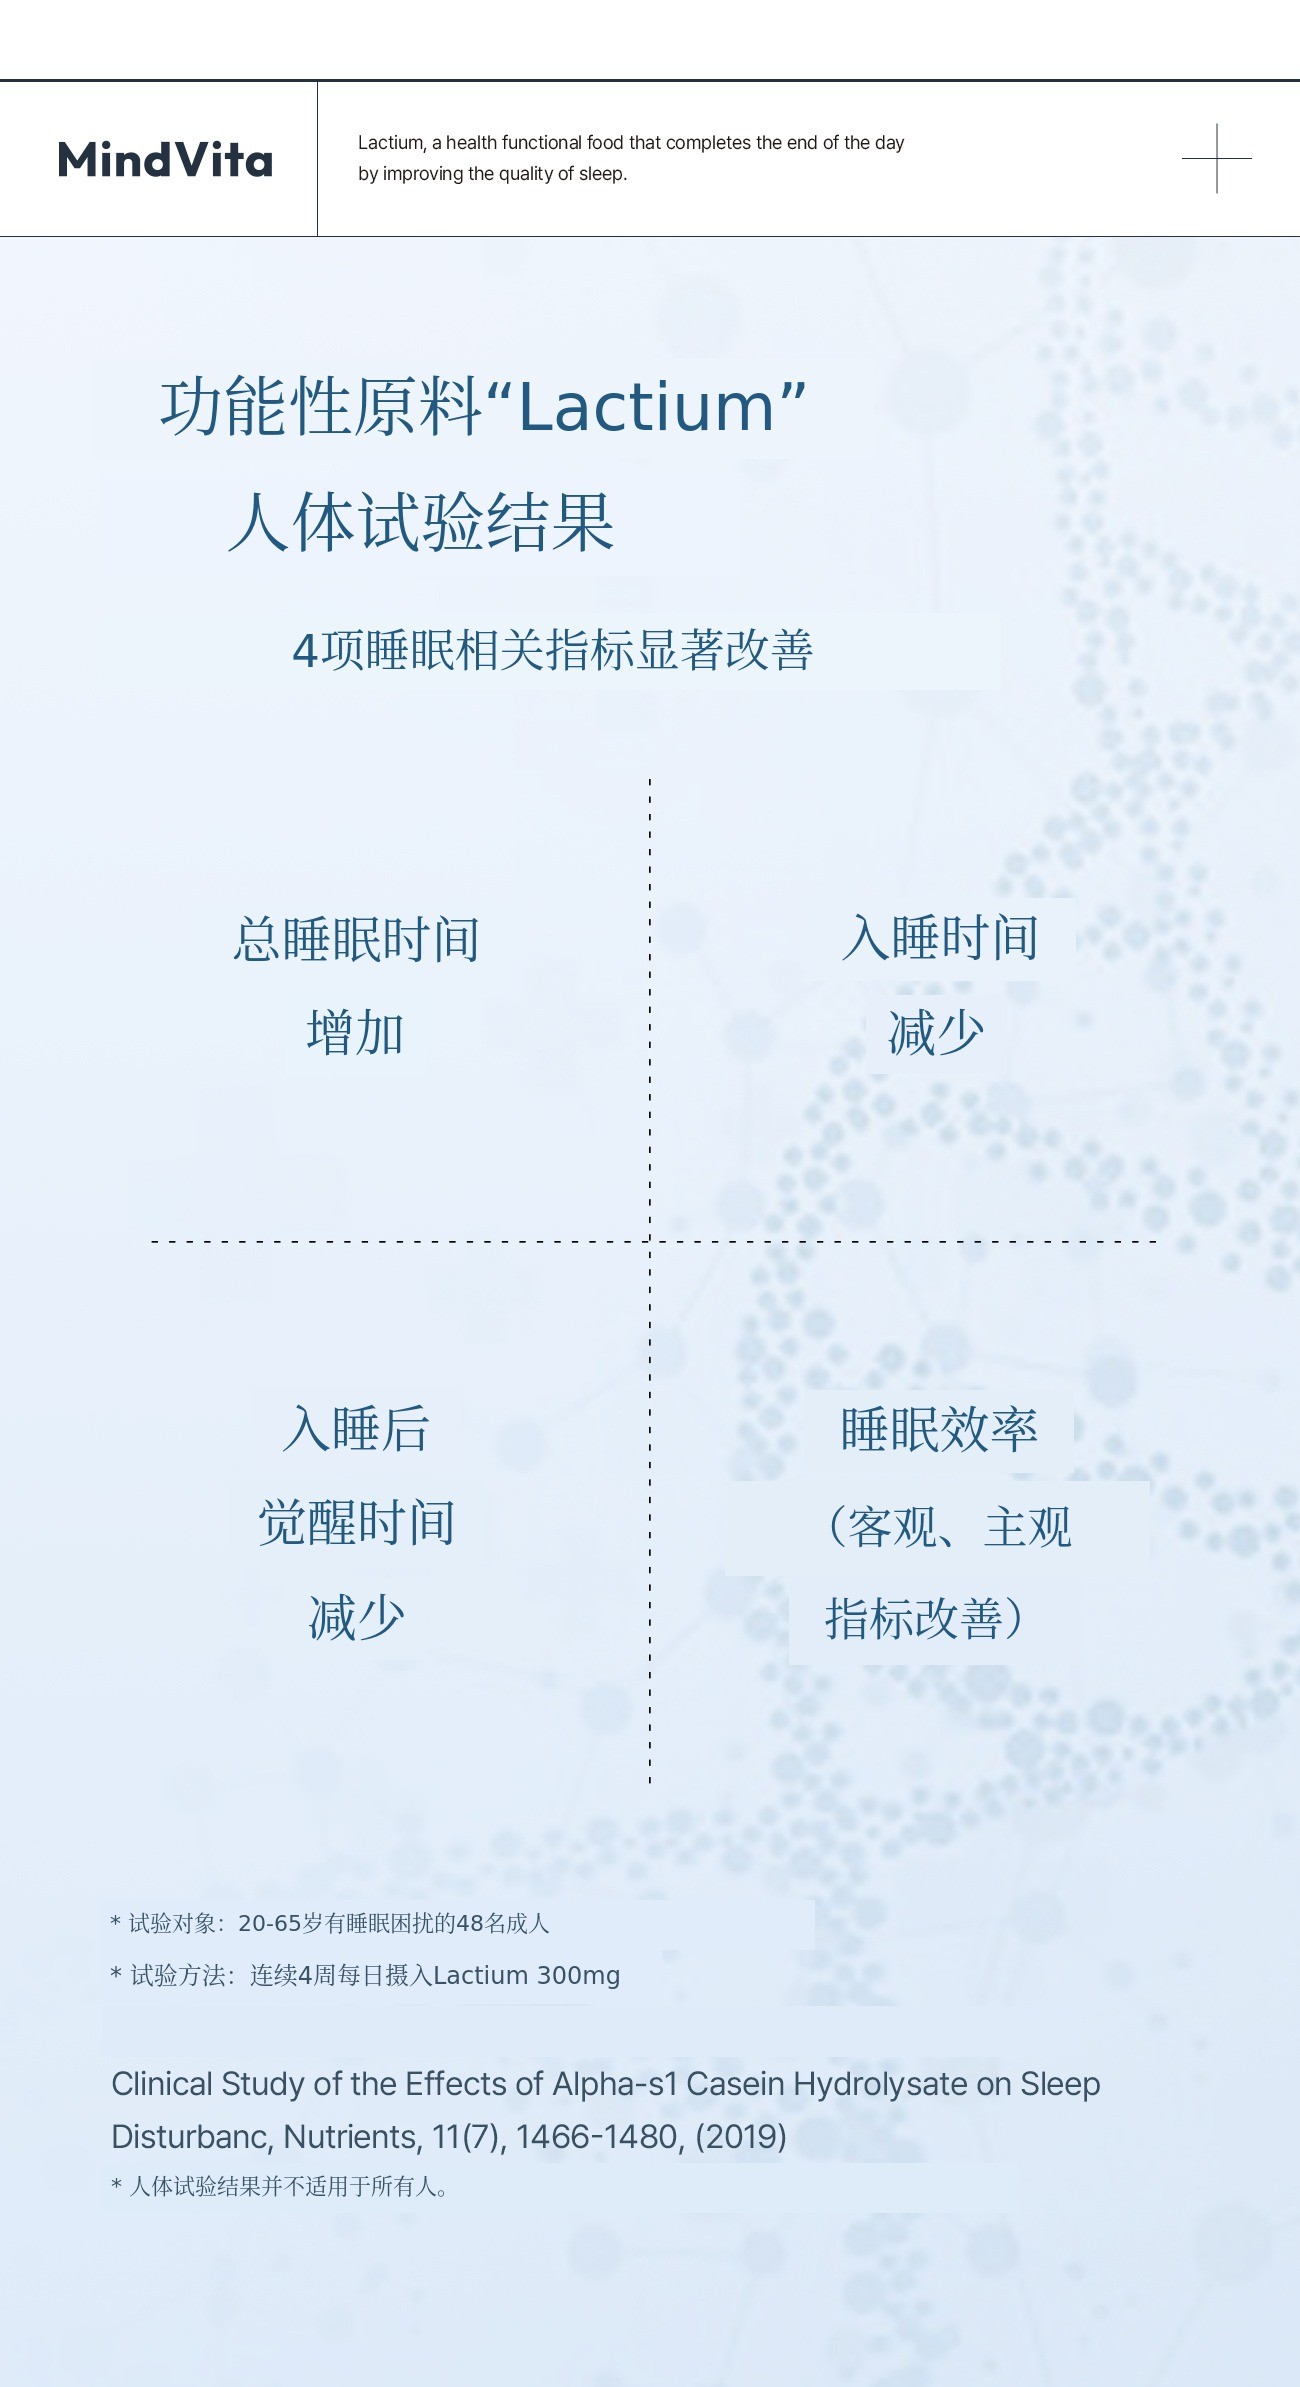

主要成分Lactium 是通过酶分解牛奶蛋白获得的乳蛋白水解物,属于天然成分,能够抑制压力激素皮质醇的过度分泌,缓解紧张和焦虑,带来心理安定感。同时通过与大脑GABA受体的间接作用,温和降低妨碍睡眠的觉醒状态,无嗜睡或依赖性,自然引导入睡是其特点。